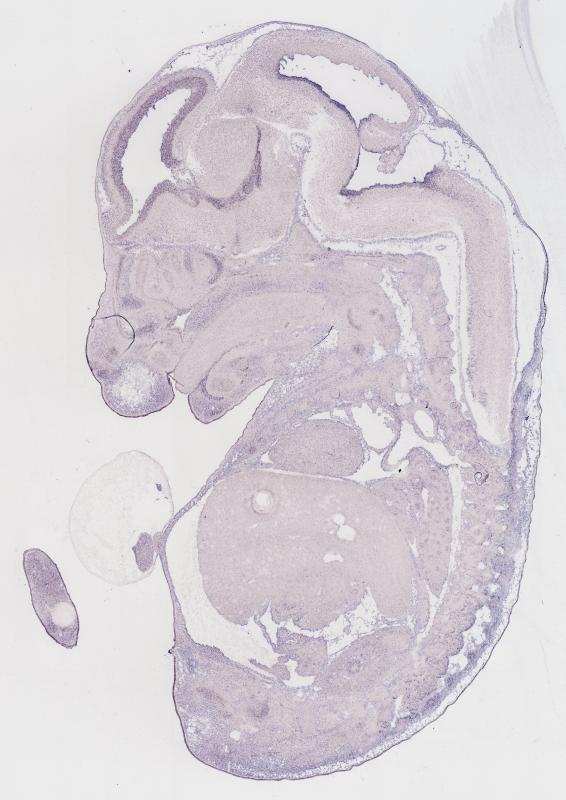

Specimen

MH837; Specimen C1251:

embryonic day 14.5